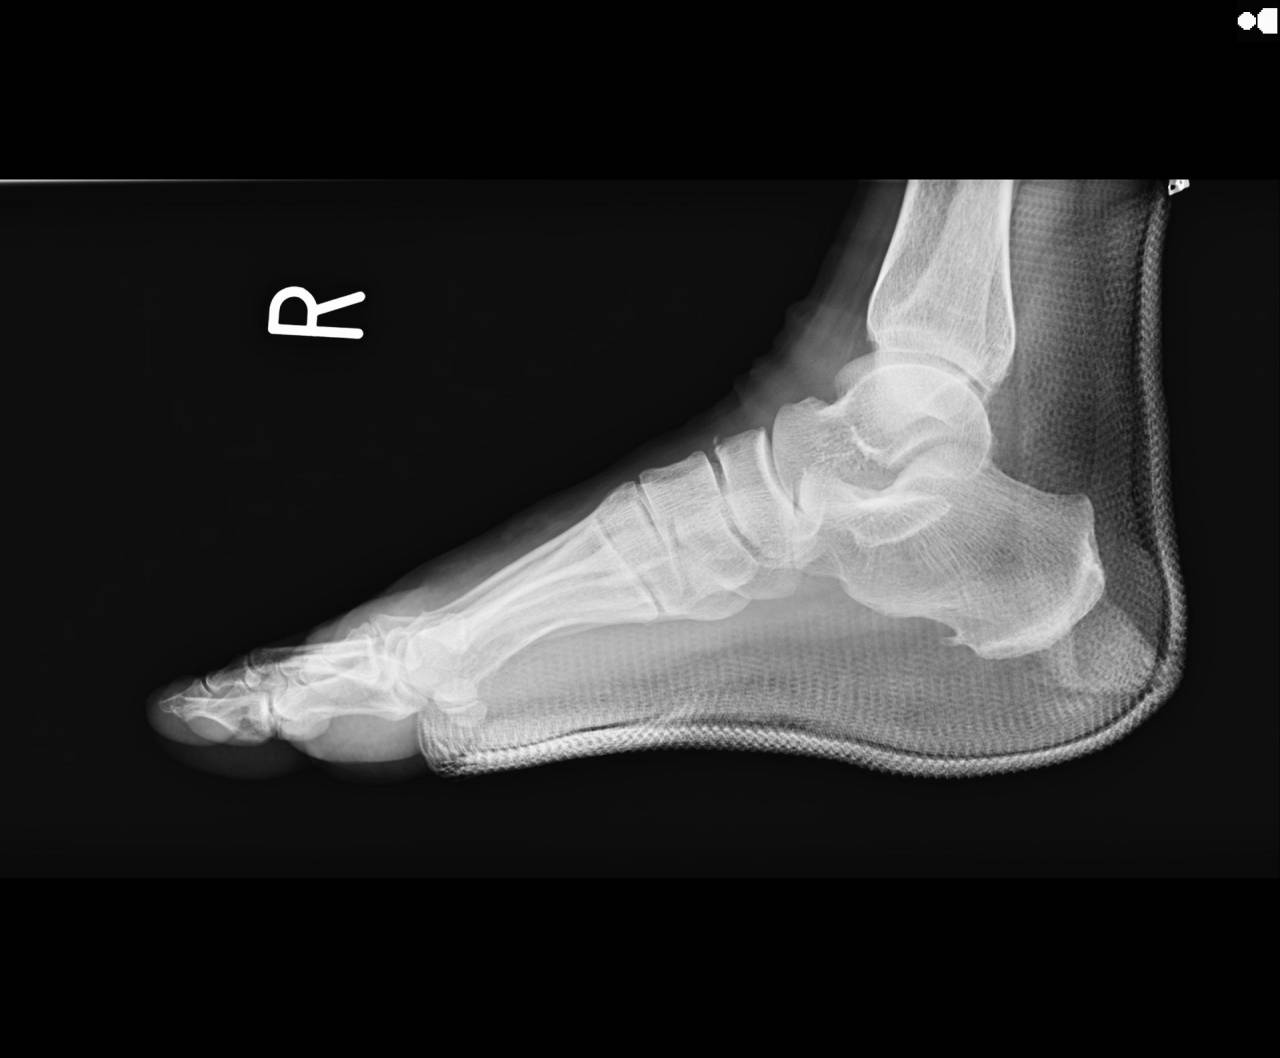

骨折の疑いがあったので当整骨院が提携している病院にてレントゲン検査をしてもらいました。

撮影した画像を確認すると踵骨前方突起、舟状骨に骨折が確認され、立方骨も骨損傷があるとのことでした。

骨折として施術を進めていきます。